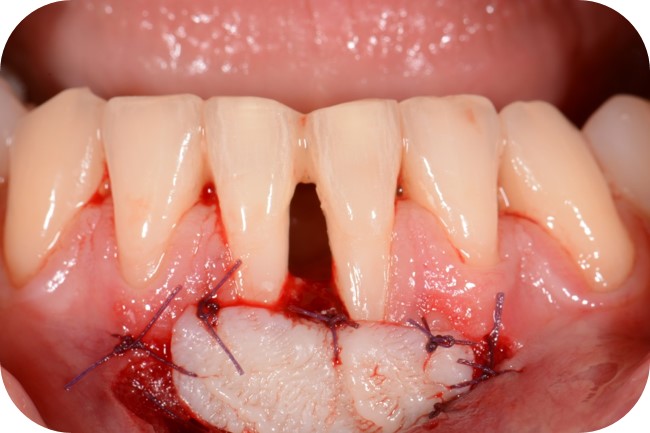

06/12 - Soft tissue augmentation with mucoderm® collagen matrix.Two-wall intrabony defect treated using cerabone® and Straumann® Emdogain® - Dr. D. Rakasevic & Prof. Dr. S. Jankovic